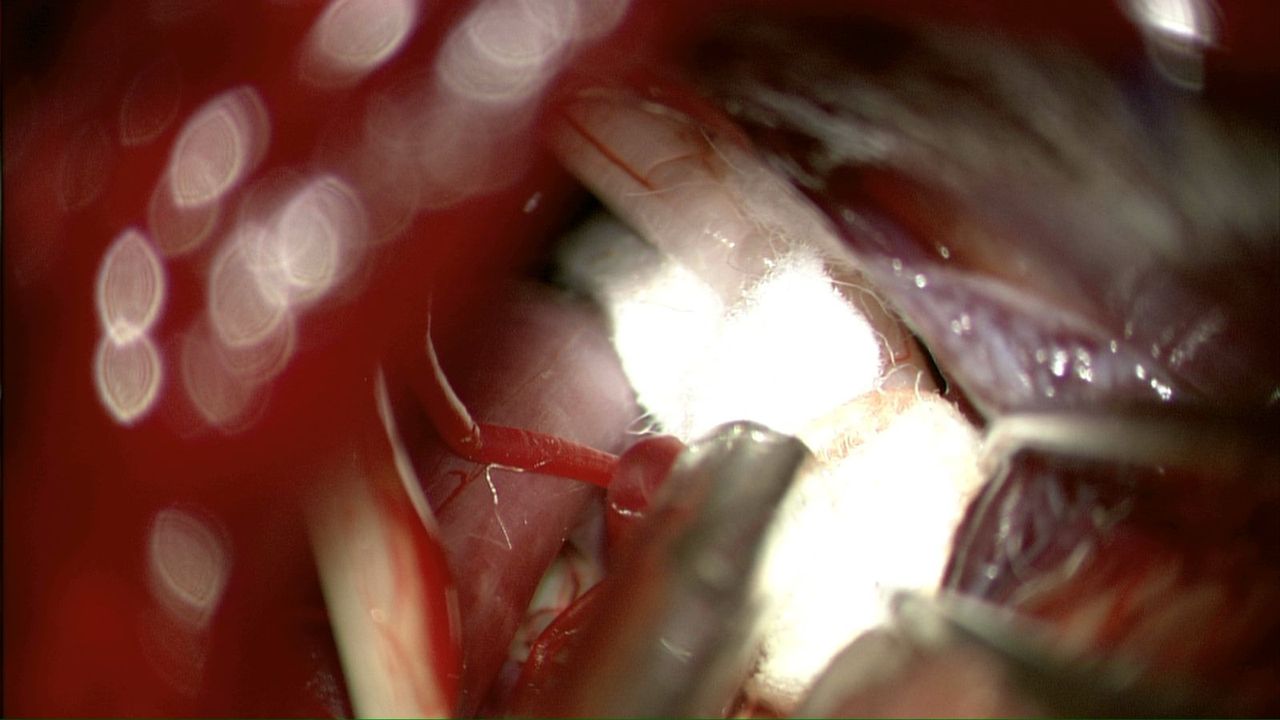

Cirugía cerebral

El neurocirujano realiza diversos tipos de cirugía craneal, según la enfermedad del paciente. Entre las más comunes están la resección de tumores cerebrales, el clipaje de aneurismas para prevenir hemorragias, la cirugía de epilepsia, drenaje de hematomas, y la colocación de válvulas en casos de hidrocefalia. También se tratan malformaciones vasculares, neuralgias y algunos casos de traumatismo craneal. Cada procedimiento se adapta al caso, buscando siempre el mejor resultado con la menor invasión posible.